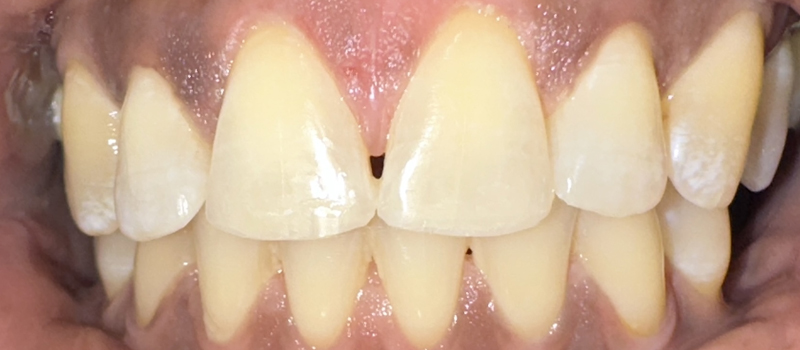

The doctor recommended a deep cleaning (scaling and root planing) to treat the infection below my gums. When they showed me before and after photos from my teeth, I was shocked! The difference was incredible—I couldn’t believe how much healthier the gums looked after treatment. It opened my eyes.

Before

After